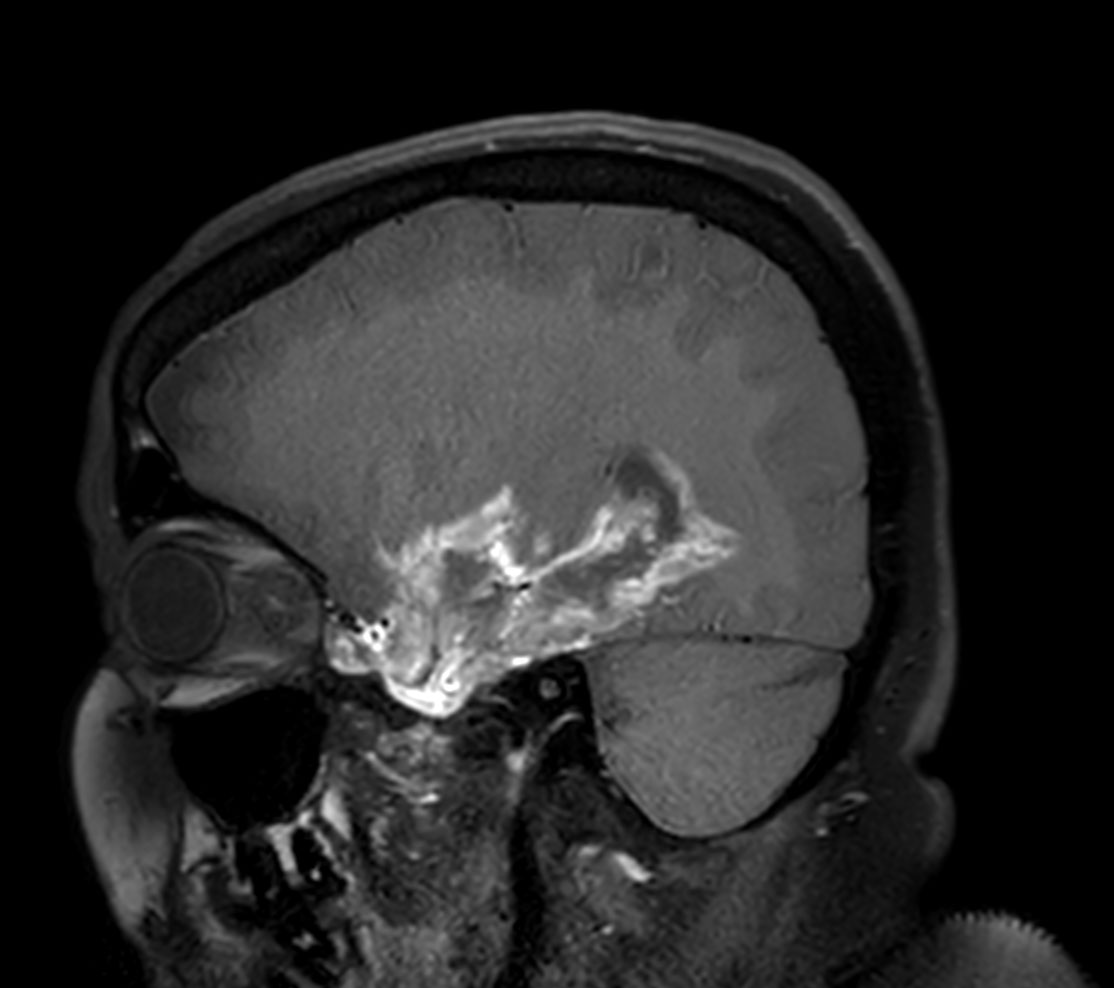

Sagittal T1w 3D TFE with gado

-